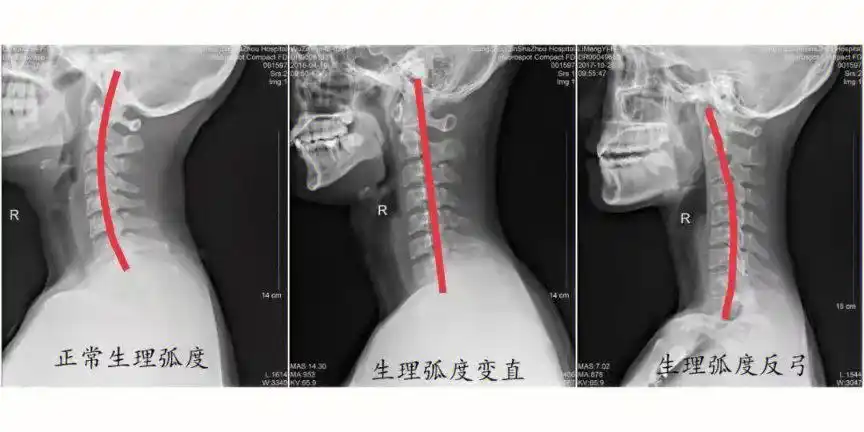

人体正常的颈椎骨受生理需要,存在弯曲弧度.

1.颈椎曲度